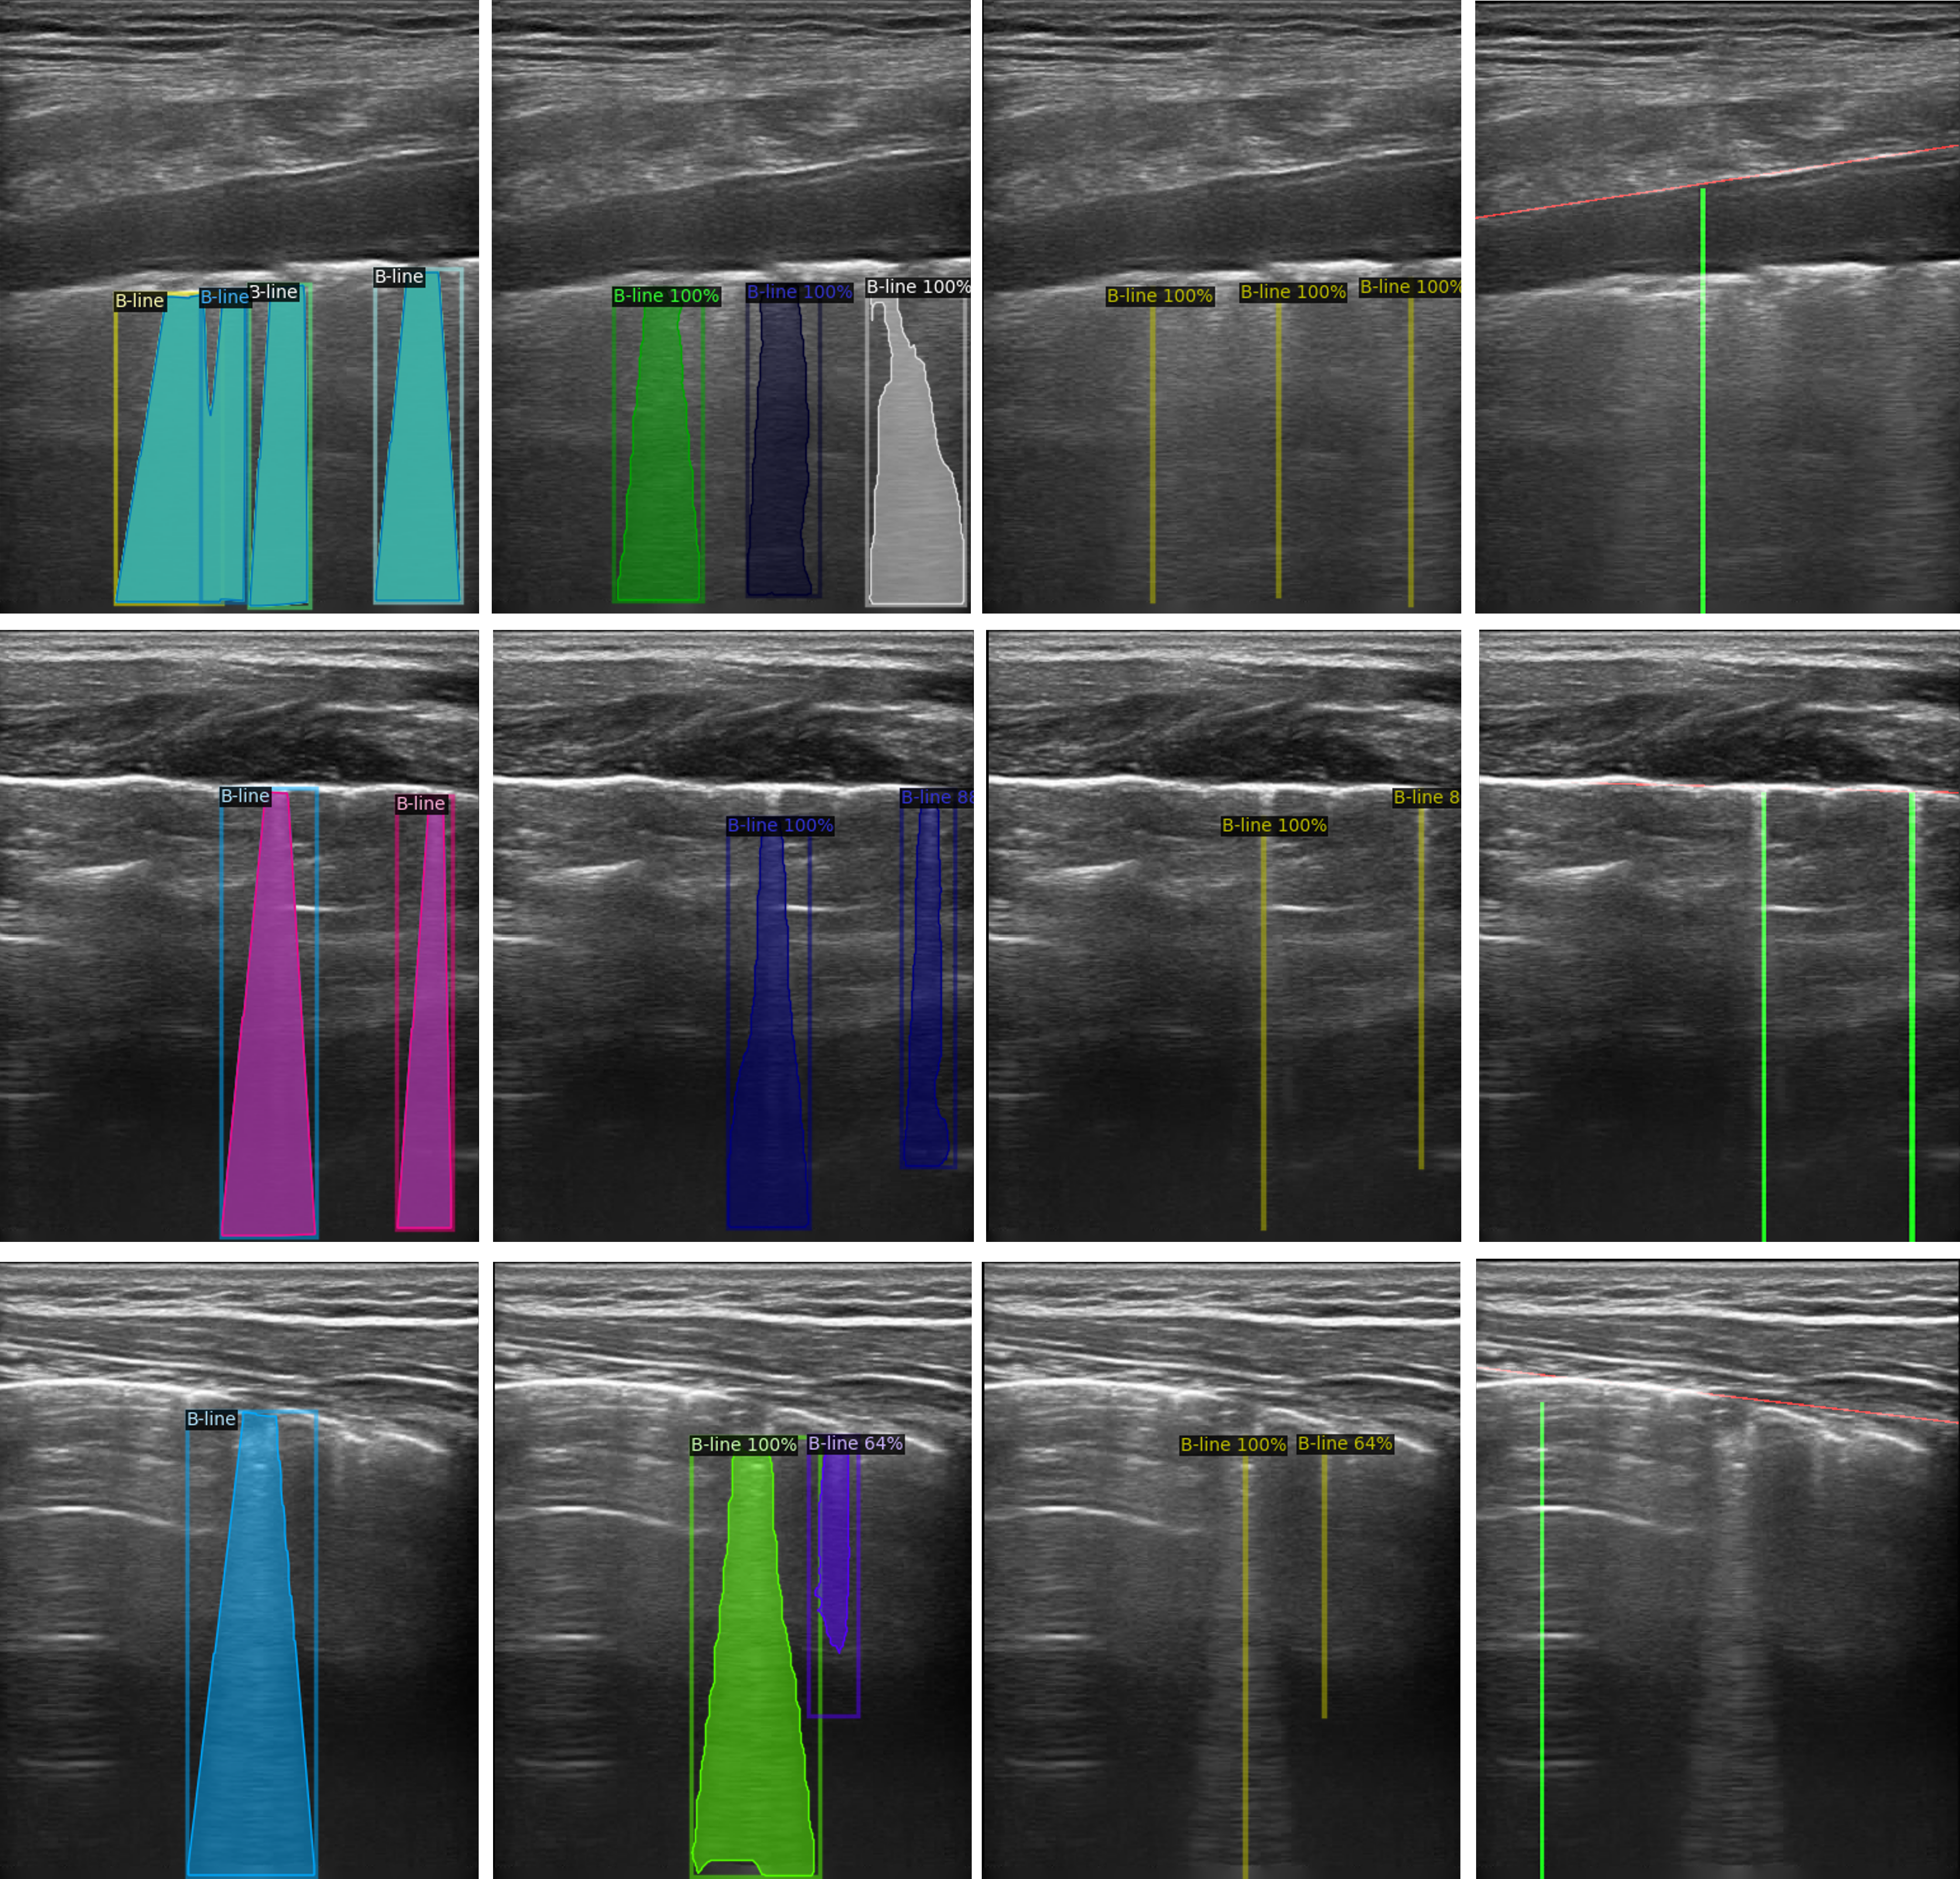

Fig. 3 shows some examples of the detected B-lines. It is obvious that the method in [14] relies heavily on localising the detected pleural line, which may result in a wrong position or in classing a vertical artifact as a B-line. In contrast, our method detects B-lines without the need for localising pleural lines and has the ability to distinguish the true B-lines from the bright vertical lines that only look similar to B-lines. Nevertheless, for some obscure B-lines, our method still presents some miss detections or false positives.

Refer to caption

Fig. 3: B-line detection results. From left to right, each column represents ground truth, B-line detection results of the proposed method in segmentation form, B-lines detection results of the proposed method shown as center line and the model-based method [14] respectively.